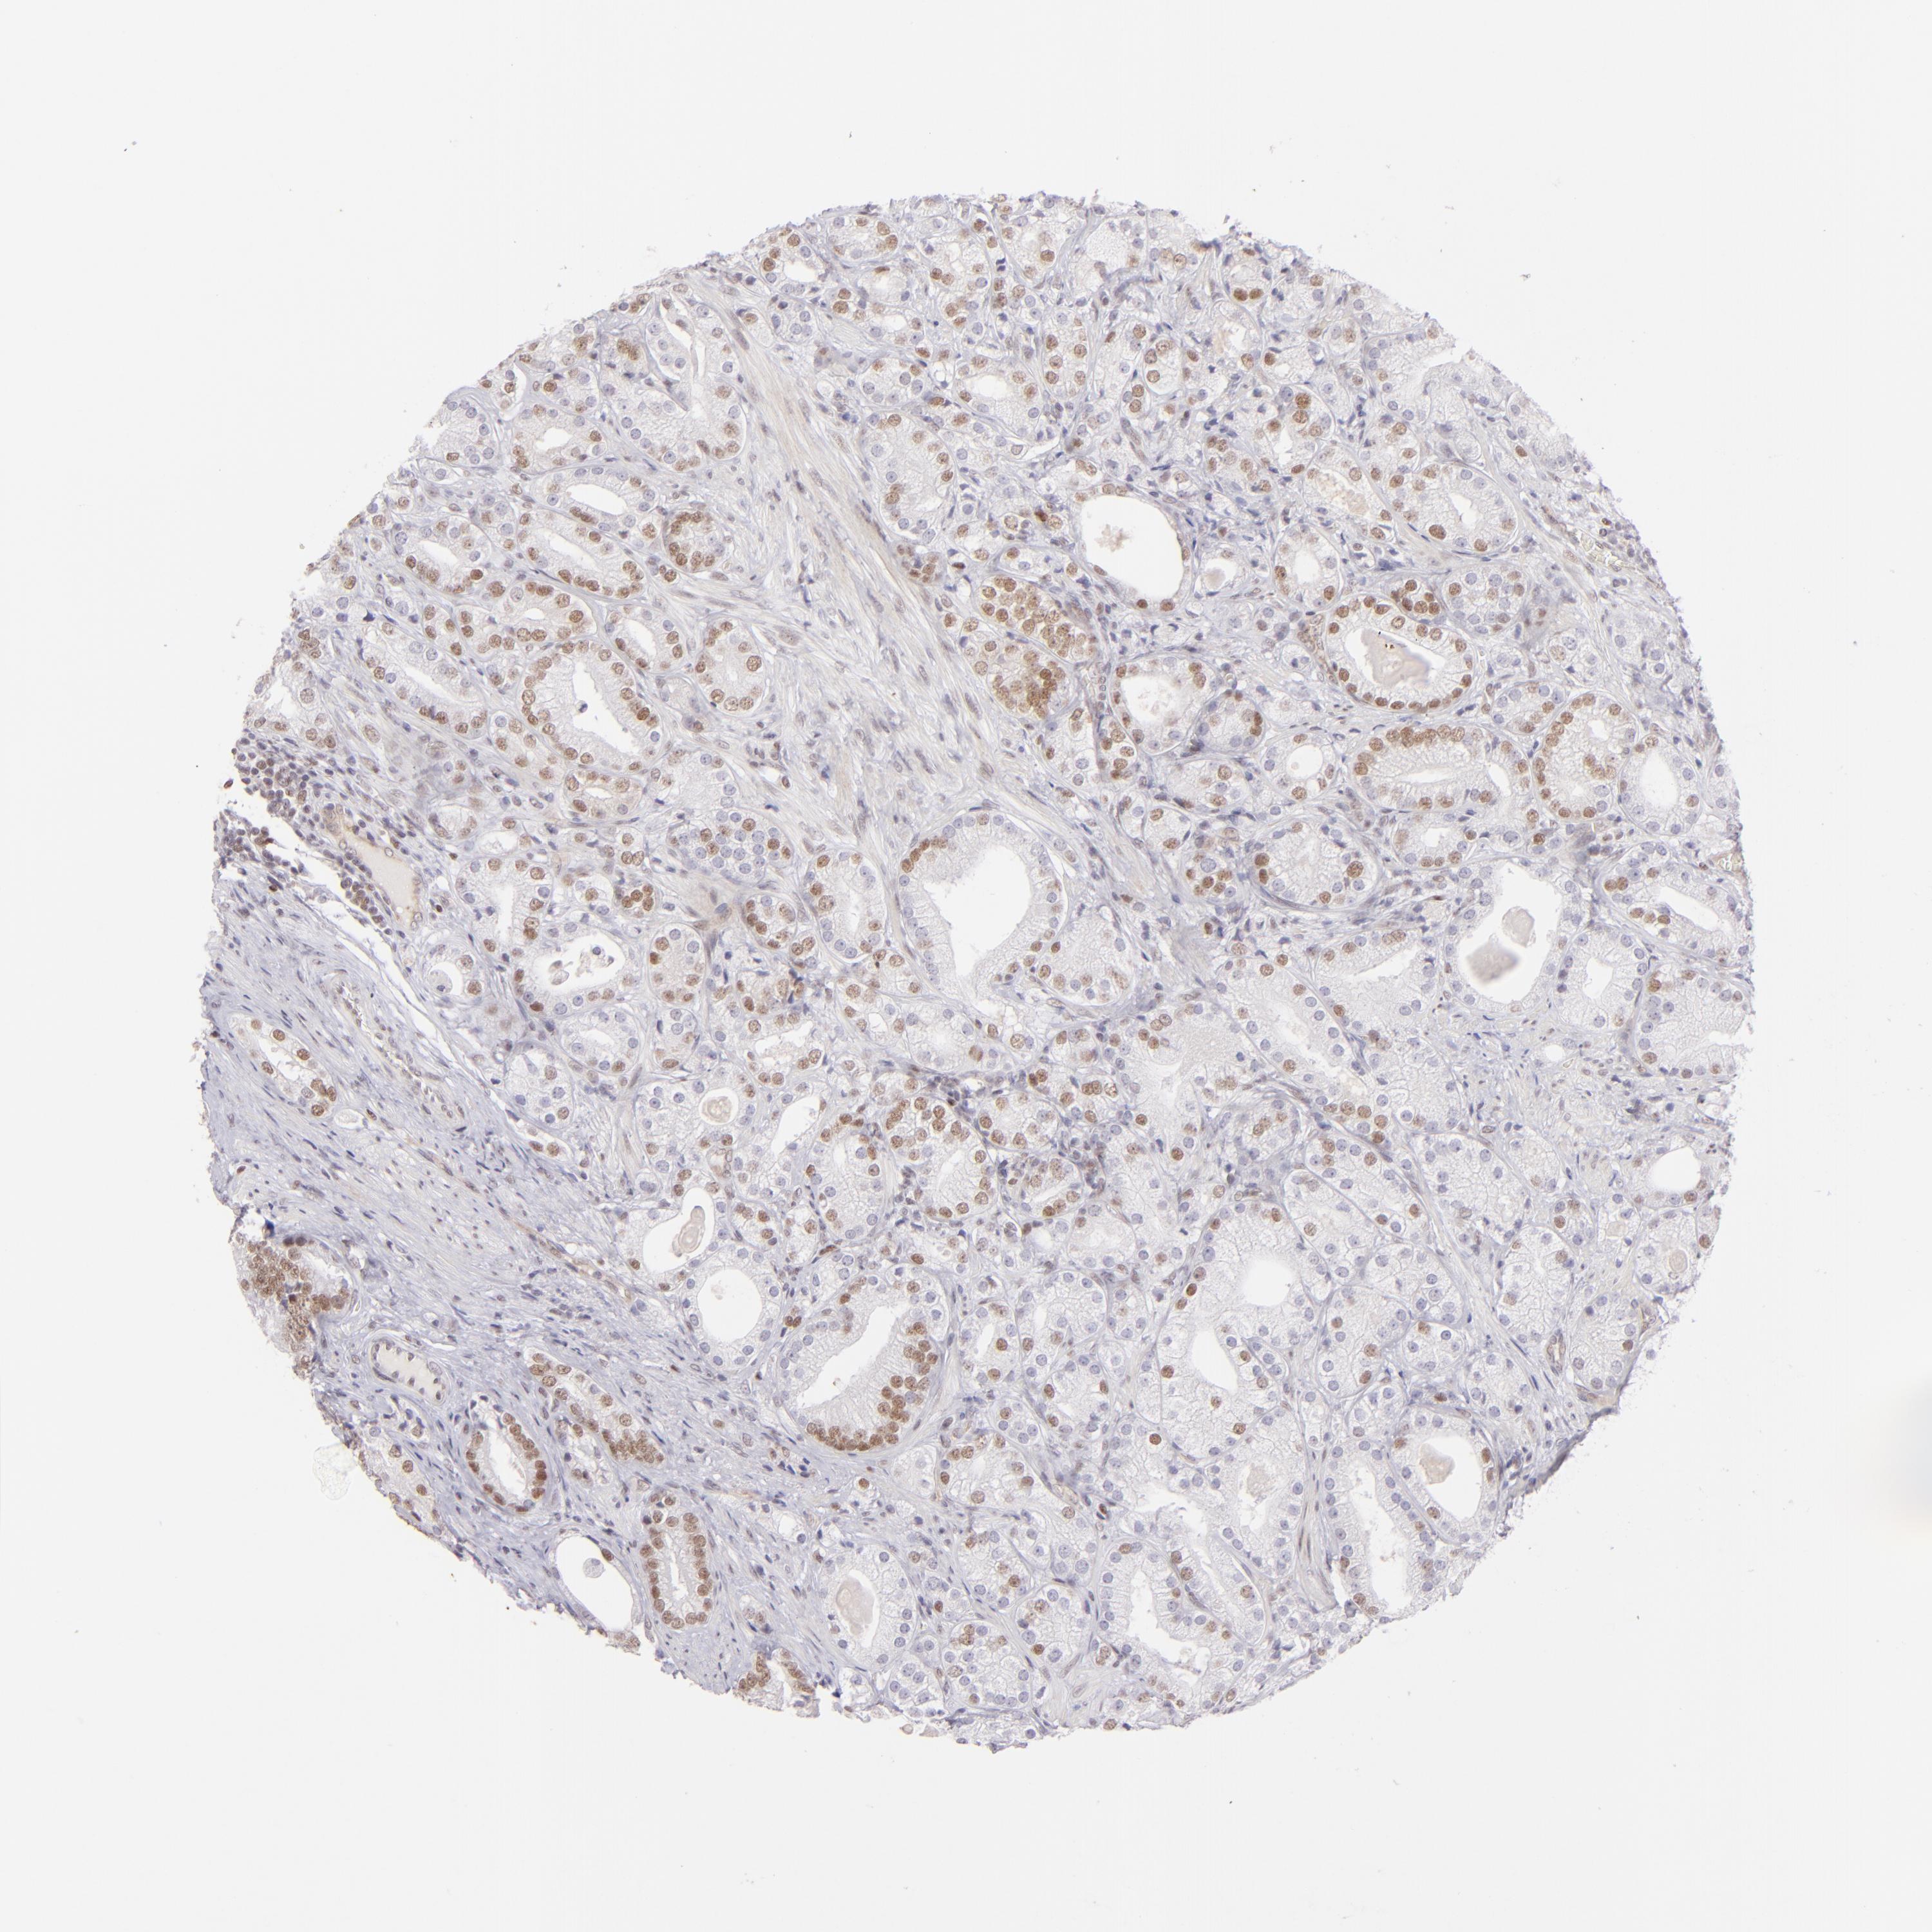

PROSTATE CANCER - Protein expressioni

A mouse-over function shows sample information and annotation data. Click on an image to view it in a full screen mode. Samples can be filtered based on level of antibody staining by selecting one or several of the following categories: high, medium, low and not detected. The assay and annotation is described here.

Note that samples used for immunohistochemistry by the Human Protein Atlas do not correspond to samples in the TCGA dataset.

Antibody stainingi

Antibody staining in the annotated cell types in the current human tissue is reported as not detected, low, medium, or high, based on conventional immunohistochemistry profiling in selected tissues. This score is based on the combination of the staining intensity and fraction of stained cells.

Each image is clickable and will lead to virtual microscopy that enables deeper exploration of all samples and also displays staining intensity scores, fraction scores and subcellular localization as well as patient and tissue information for each sample.

Antibody HPA064323

Antibody CAB002608

Staining

High

Medium

Low

Not detected

Intensity

Strong

Moderate

Weak

Negative

Quantity

>75%

75%-25%

<25%

None

Location

Nuclear

Cytoplasmic/membranous

Cytoplasmic/membranous,nuclear

Adenocarcinoma, High grade

Adenocarcinoma, Low grade

Adenocarcinoma, Medium grade